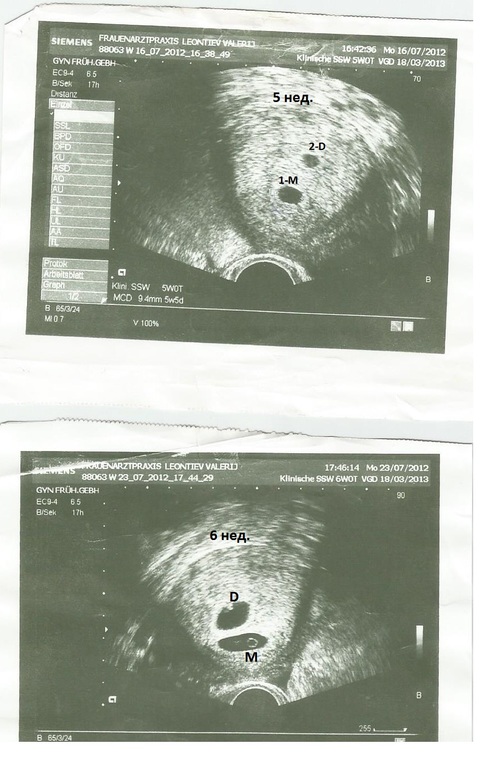

Двое? Посмотрите узи кто может, нам 6 недель

УЗИ, КТГ, доплер, скрининг, ХГЧ и другие анализыСегодня была на узи, что бы убедиться что беременность маточная и все в порядке а меня огорошили, что может быть двойня!!! Я вообще вижу три затемнения, а Г сказал что одна беременность хорошая четкая, а вот вторая должна проясниться за неделю (сказал приходить через неделю)

Ритта а на узи стоит D и M это значит девочка и мальчик или что то другое ? Вроде на этом сроке еще и сердечко не всегда слышно?

Ага,девочка и мальчик.Сердца и не было слышно,просто я знаю,что мальчик идёт по развитию постарше,он по всем УЗИ шёл на 3 дня старше,первый,крупнее,поэтому я проштудировала и прочитала в инете,что с двойней разница в оплодотворении может быть два-три дня,яйцеклетки,две,не обязательно вышли в один день,а мы тогда каждый день на совесть "делали"